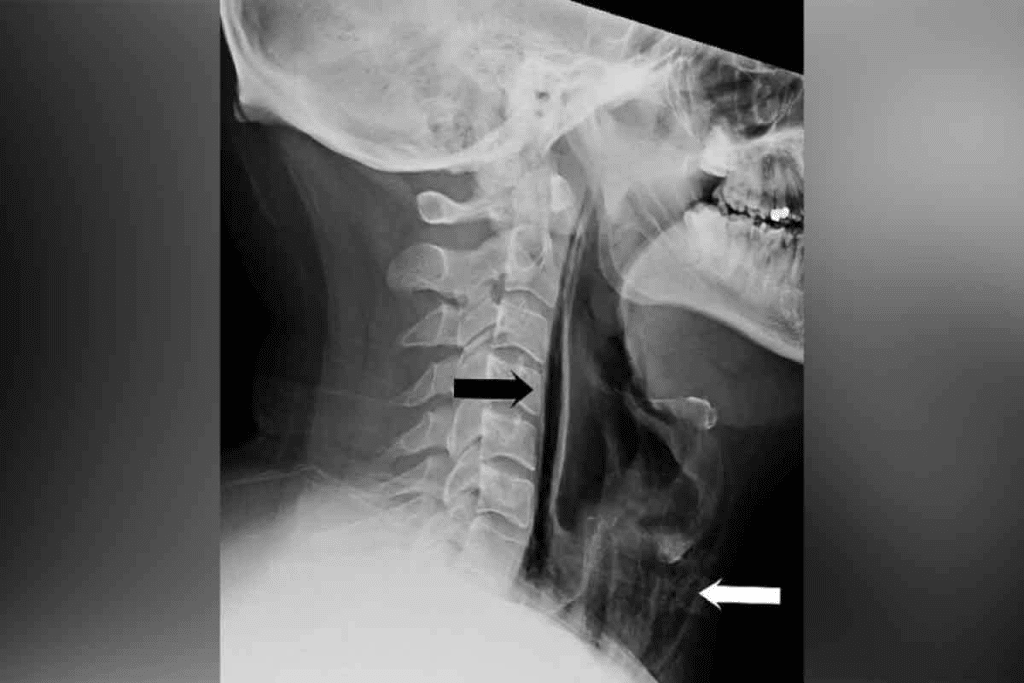

X-rays and Barium Swallow Studies for Throat Cancer

X-rays and barium swallow studies are old tools used to check for throat cancer. They are not as good as newer methods, but they help start the process of finding out if you have cancer.

The Role of Traditional X-rays in Initial Assessment

X-rays have been around for a long time. They help find big problems in the throat that might mean cancer. But, they can’t show details of soft tissues well.

We start with X-rays because they are fast and easy to get. They can spot big issues that need more detailed tests.

How Barium Swallow Studies Work

A barium swallow study is a special X-ray of the esophagus and throat. You drink a special liquid that shows up on X-rays. Then, X-rays are taken as you swallow to see how your throat works.

This test helps find problems with swallowing and looks at the throat’s shape. But, it’s not enough to say for sure if you have throat cancer.

Limitations of X-ray Technology in Cancer Detection

X-rays and barium swallow studies give some clues, but aren’t enough to find or understand throat cancer. They can’t spot early cancers or see how far cancer has spread.

For a full look at throat cancer, we need better tools like CT scans, MRI, or PET scans.